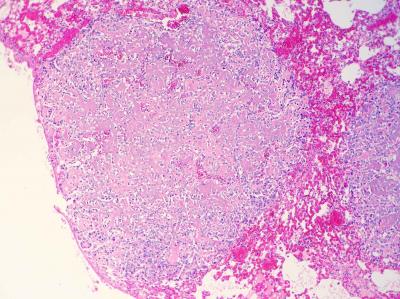

Después de muchos años de trabajo en diagnóstico con estos 131 anfibios, frecuentemente procesados en cortes transversales seriados de todo su cuerpo, hemos aprendido mucho sobre enfermedades de anfibios. Pasaron años también de dedicación a este estudio, probablemente meses de mi vida empleados en documentar fotográficamente esta casuística ... todo un reto trabajando en un servicio de diagnóstico especializado con alrededor de 1600 casos anuales en los últimos años para un único patólogo, y cuidando de dos personitas muy necesitadas de jugar. La primera parte, dedicada a las enfermedades infecciosas y parasitarias, ha sido recientemente publicada en la revista Clínica Veterinaria de Pequeños Animales (40(1):15-27, 2020) de AVEPA; con este estudio, nuestro deseo era ofrecer unos materiales de diagnóstico basándonos en la imagen, en color, y en tópicos prácticos útiles para divulgar medicina de anfibios en lengua española. Nos honra haber recibido el 2º Premio de la XXIII Edición del Premio Científico AVEPA – Miguel Luera por este artículo, lo que me permite recuperar la ilusión del concepto de patología para conservación y que no quede en meras palabras. Este logro lo es para conservación. Esperamos que pronto se llegue a publicar la segunda parte de este estudio, que incluye el resto de enfermedades diagnosticadas en estos 131 pacientes. Agradezco a tantas personas que habéis remitido casos de anfibios (¡y otras muchas especies!) a Noah's Path durante tanto tiempo; a mi laboratorio de histotecnología Synlab Diagnósticos Globales por su extraordinario trabajo en las preparaciones histológicas; a mis residentes en rotación de UNAM Celic Berenice Montoya, Mayra Chávez y Rubén Arturo López por ser esenciales en mantener a flote Noah's Path en los años más difíciles; a mis grandes maestros Alberto Marco, Mariano Domingo y Pepe Ramos en la Universitat Autònoma de Barcelona por inculcarme las bases esenciales del conocimiento y forma de trabajar en patología; a Amy Camacho y Alberto Parás con nuestro Africam Safari y toda mi gente de México por 4 años maravillosos de mi vida que hicieron expresar y crecer mi personalidad; a mi mentor Mike Garner por tantas enseñanzas como patólogo y como padre, y sobre todo por su amistad - o más bien hermandad -, inquebrantable durante ya más de 22 años, y por su fantástico sentido del humor; y a mi maravillosa familia por hacer posible y motivarme de forma esencial para esta dedicación y este logro, muy especialmente a mi mamá Maite - "a la mare" - y a su amiga-hermana María, que han sido un extraordinario ejemplo de dedicación, abnegación, constancia, organización, honestidad, bondad y altruismo. Y a mis personitas muy necesitadas de jugar, les pido sobre todo que cuando se hagan mayores se acuerden mucho de Compostito y por qué son tan importantes los anfibios en nuestro planeta.

En este estudio retrospectivo realizado uniendo la casuística de Mike Garner (Northwest ZooPath) y Noah's Path, se identificaron 29 casos de infección renal ascendente por protozoos flagelados en reptiles, mayoritariamente tortugas y camaleones. En numerosos casos, los flagelados se asociaban a nefritis túbulo-intersticial e incluso gota y mineralización de tejidos blandos, y, por lo tanto, se consideraron relevantes o incluso involucrados en la muerte de los animales afectados. Podéis encontrar más información en: Juan-Sallés C, et al: Renal flagellate protozoan infection in reptiles: 29 cases. Journal of Zoo and Wildlife Medicine 45(1):100-9, 2014.